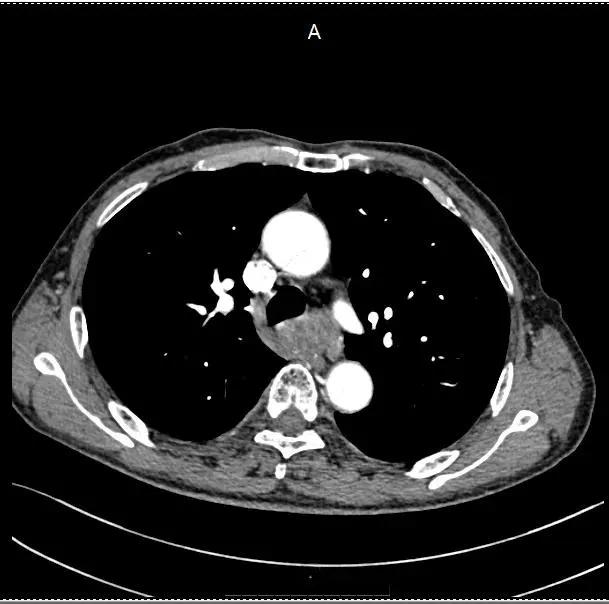

CT扫描结果显示,在患者的后纵隔区域有一个约5厘米大小的肿块,边界清晰,密度均匀略低。进一步的增强CT显示,肿块在注射造影剂后有中度强化。这些特征提示医生,这个肿块很可能是神经源性肿瘤。

为了获得更详细的影像信息,医生又为患者安排了MRI检查。MRI的多序列成像能力为医生提供了丰富的信息:肿块主要位于脊柱旁,与脊髓有明显的分界,内部结构清晰,没有明显的坏死或囊变。这些发现进一步支持了神经源性肿瘤的诊断。